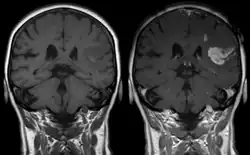

Effect of contrast agent on images: Defect of the blood–brain barrier after stroke shown in MRI. T1-weighted images, left image without, right image with contrast medium administration.

Gadolinium-based pharmaceuticals alter the relaxation time, and hence spectral line shape, of those protons that are in water molecules that are transiently attached to the paramagnetic atoms, resulting contrast enhancement of the MRI image.[11] This allows better visualisation of some brain tumours.[11]